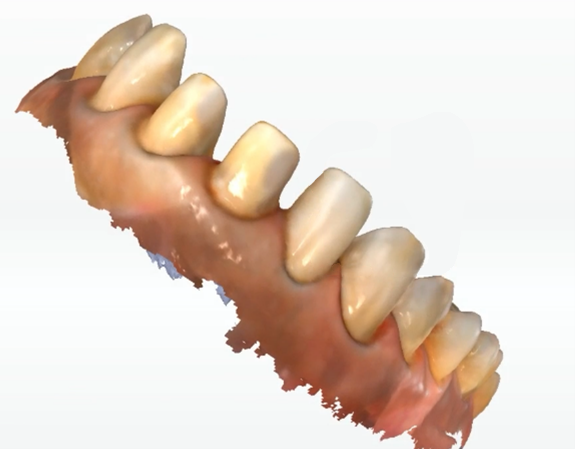

ステップ2: コンピュータ支援デザイン

ベニアの設計中に、モックアップデータをインポートして、最終的なプロテーゼが患者の期待を満たしていることを確認します。